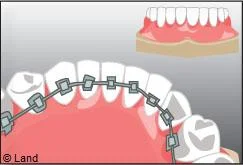

Il s’agit d’un appareil multi-attaches appelé communément « bagues ». Il permet de déplacer très précisément chaque dent. Chaque dent est équipée d’une attache appelée « bracket ». Les dents vont être mobilisées par l’utilisation de fil métallique dont l’alliage, la section, la forme sont déterminés par les différentes étapes du traitement. Ils seront insérés dans les attaches par le biais de ligatures élastiques, métalliques ou d’un mini-clip. Les « brackets » utilisés chez les adolescents sont la plupart du temps métalliques mais ils peuvent être remplacés avantageusement par des éléments transparents ou de la couleur des dents.

La technique linguale offre la possibilité d’un appareil orthodontique efficace et totalement invisible.

Elle permet la pose de bagues sur la face interne des dents. Elle est souvent utilisée pour les traitements de l’adulte rebutés par le port d’un appareil visible. Cette technique difficile à mettre en ?uvre et peu confortable pour le patient, a fortement évolué ces dernières années, notamment grâce à la conception et à la réalisation assistées par ordinateur. On peut donc aujourd’hui traiter tous les patients qui le souhaitent en lingual.